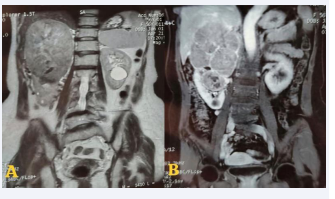

An MRI carried out to better for staging the tumor, classified the tumor as T3aN0M0 (Figure 2).

Figure 2 A. T2: Heterogeneous right upper and middle renal mass  measuring 145*124*112mm restricting diffusion, contains a necrotic  center. B.T1 FS Gado+: enhancement after Gadolinium injection.

Figure 2: A. T2: Heterogeneous right upper and middle renal mass measuring 145*124*112mm restricting diffusion, contains a necrotic center. B.T1 FS Gado+: enhancement after Gadolinium injection.